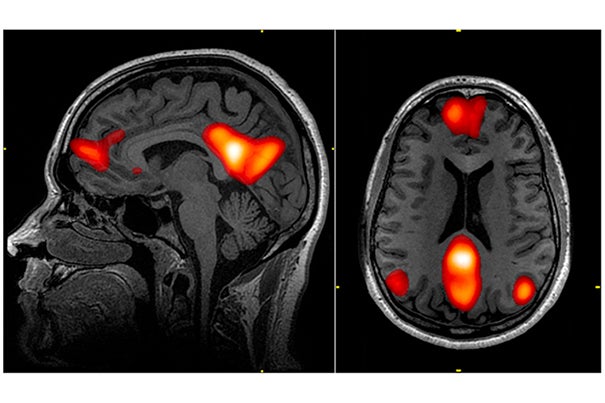

Functional magnetic resonance imaging (fMRI) is a very popular non-invasive tool used to image functionally active brain regions. They use the BOLD method which means blood oxygenation level-dependent and it relies on hemoglobin as the endogenous contrast agent. Specifically observing the magnetization difference between oxygenated and deoxygenated hemoglobin. Exact nature of this occurrence is still unknown, but BOLD responses increase directly with neural activity correlating particularly with local field potential (LFP) measures. These measures represent synchronized synaptic inputs. Another method known as Evoked potentials are very similar to LFPs but are from extracellular currents from summated postsynaptic potentials – in turn representing a population of synaptic activity rather than neuronal firing states.

Best current resolution is level of one cortical column containing 10^5 neurons. Most compromise shorter acquisition times meaning the shot would take longer thus less temporally accurate, for a spatial resolution of 8-50mm^3 containing at least 10^6 neurons. MRI Voxels: An MRI image is composed of a number of voxels; the voxel size is the spatial resolution of the image. A voxel is a 3D unit of the image with a single value, just as for digital photographs a pixel is a 2D unit of the image with a single value. Given the scale of imaging for an effect to be seen, it is still unclear if this technology could differentiate large changes in small populations of cells or small changes in a large population of cells.